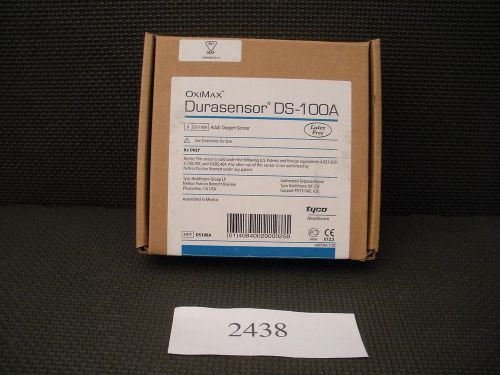

Nellcor OxiMax Durasensor DS-100A Adult Oxygen Sensor Finger